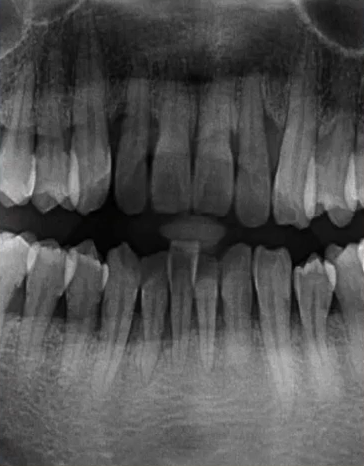

上颌前牙区、下颌前牙区牙位辨认

患者处于混合牙列期,可以看到右侧前牙区有多生牙,下颌有融合牙的存在。